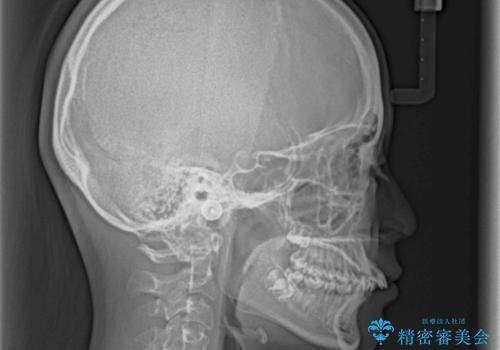

奥歯の咬み合わせを見ると、上顎が下顎に対して相対的に前方にありました。

深い咬み合わせを改善するためには、上顎臼歯を後方に移動させつつ、下顎の小臼歯を直立させる必要があります。

インビザライン単体で対応ることも検討できますが、達成する可能性が低いため、カリエールディスタライザーという補助装置を併用して、より確実性を上げることとしました。

奥歯の咬み合わせと深い咬み合わせを改善した後、インビザラインで歯列を整えることとしました。